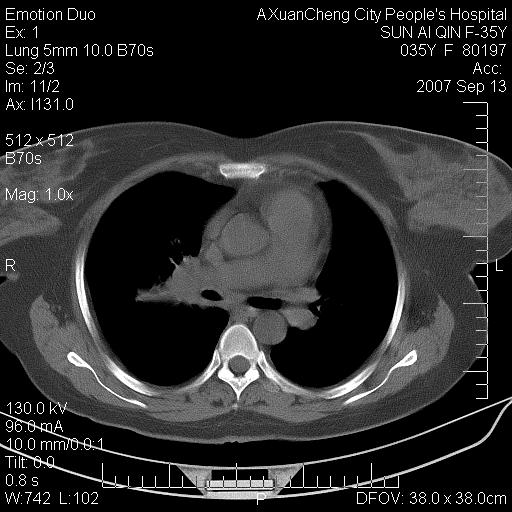

以下是引用天南地北在2007-9-13 13:43:00的发言:[br]考虑双肺、肺门侵润

以下是引用ydx_74在2007-9-13 15:42:00的发言:[br]仅看片,考虑右上肺癌并双肺转移,结合病史,考虑肺门、肺内淋巴侵润

以下是引用同在2007-9-13 15:08:00的发言:[br]支持肺门及双肺侵润.